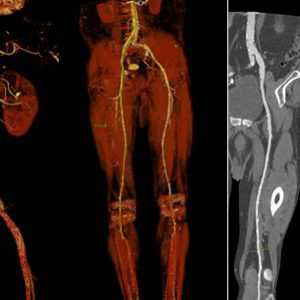

Radiology department of the Rijnland Hospital Leiderdorp and the University Medical Centre Groningen, the Netherlands.КТ-ангиография сосудов брюшной полости

КТ-ангиография сосудов брюшной полости считается одним из наиболее современных методов определения состояния здоровья сосудистой системы в указанной области. Его главным отличием выступает привлечение специального контрастного вещества.

Обычное ультразвуковое исследование не способно предоставить развернутую картину по структуре и общему состоянию сосудов в брюшной области, что способствовало разработке и внедрению технологии ангиографии. Вместе с контрастом получается визуализировать абсолютно все участки сосудистого русла. На основе полученной визуализации доктор сможет определить не только строение больших и мелких сосудов, но также выявить возможные аномалии в близлежащих органах.

После того как контрастный препарат вводят в локтевую вену, он мгновенно добирается до сердца и дальше распространяется по аорте, ее ветвям, а позднее и до капилляров в брюшине, открывая картину состояния:

- почечных сосудов;

- селезеночных сосудов;

- чревного ствола;

- верхней брыжеечной артерии;

- нижней брыжеечной артерии.

Все они, как и капилляры, отвечают за транспортировку питательных веществ к внутренним органам брюшной полости. Как только указанные кровяные пути выходят из строя, орган перестает выполнять свои обязанности должным образом, что приводит к резкому ухудшению самочувствия. Обнаружить первоисточник всех проблем позволяет тщательная визуализация, на основе которой можно выяснить следующие характеристики:

- анатомические особенности брюшных сосудов вне зависимости от размеров;

- аномалии врожденного или приобретенного типа, вплоть до удвоения и недоразвития;

- патологии на разных стадиях развития, включая локальный атеросклероз и расслоение стенок;

- процентное соотношение ступени сосудистого сужения;

- показатели нарушения кровотока;

- описание кровотока, включая скорость и уровень кровенаполнения.